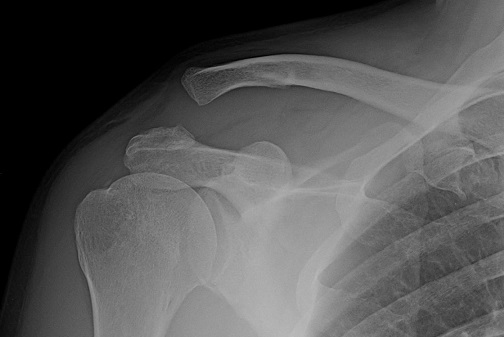

整形外科の先生から、右肩を

「

肩鎖関節脱臼・3型

」

と診断されました

この一番右の

3型

です

3本の靱帯が断裂して鎖骨が脱臼しちゃったらしい・・・

現在は右肩が全く使えません。肘と手は普通に使えますが腕が上がりません。